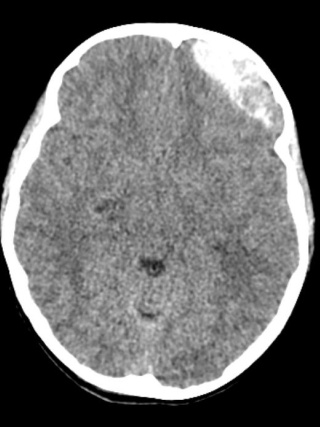

CT scan of an acute epidural hematoma in pediatric patient Eliza Andrews.

A CT scan of an acute epidural hematoma in pediatric patient Eliza Andrews.

A CT scan revealed an acute epidural hematoma. Blood was collecting between her skull and her dura mater, a layer of tissue that helps protect the brain, causing dangerous pressure on her brain that required immediate surgery.